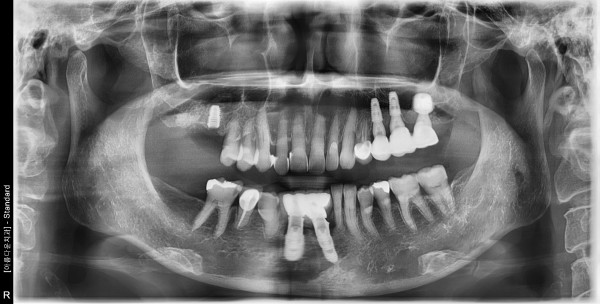

66세 여/ 상악 우측 어금니 발치, 치조골 이식술 후 보험임플란트 식립